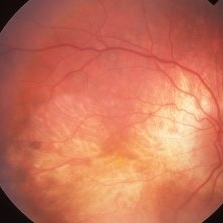

Regional Choriocapillaris Atrophy

73-year-old white female with regional choriocapillaris atrophy OS; VA= 20/100.

Imaging device: Topcon VT-50

Condition/keywords: atrophy, choriocapillaris, hereditary choroidal atrophy, hereditary choroidal dystrophy